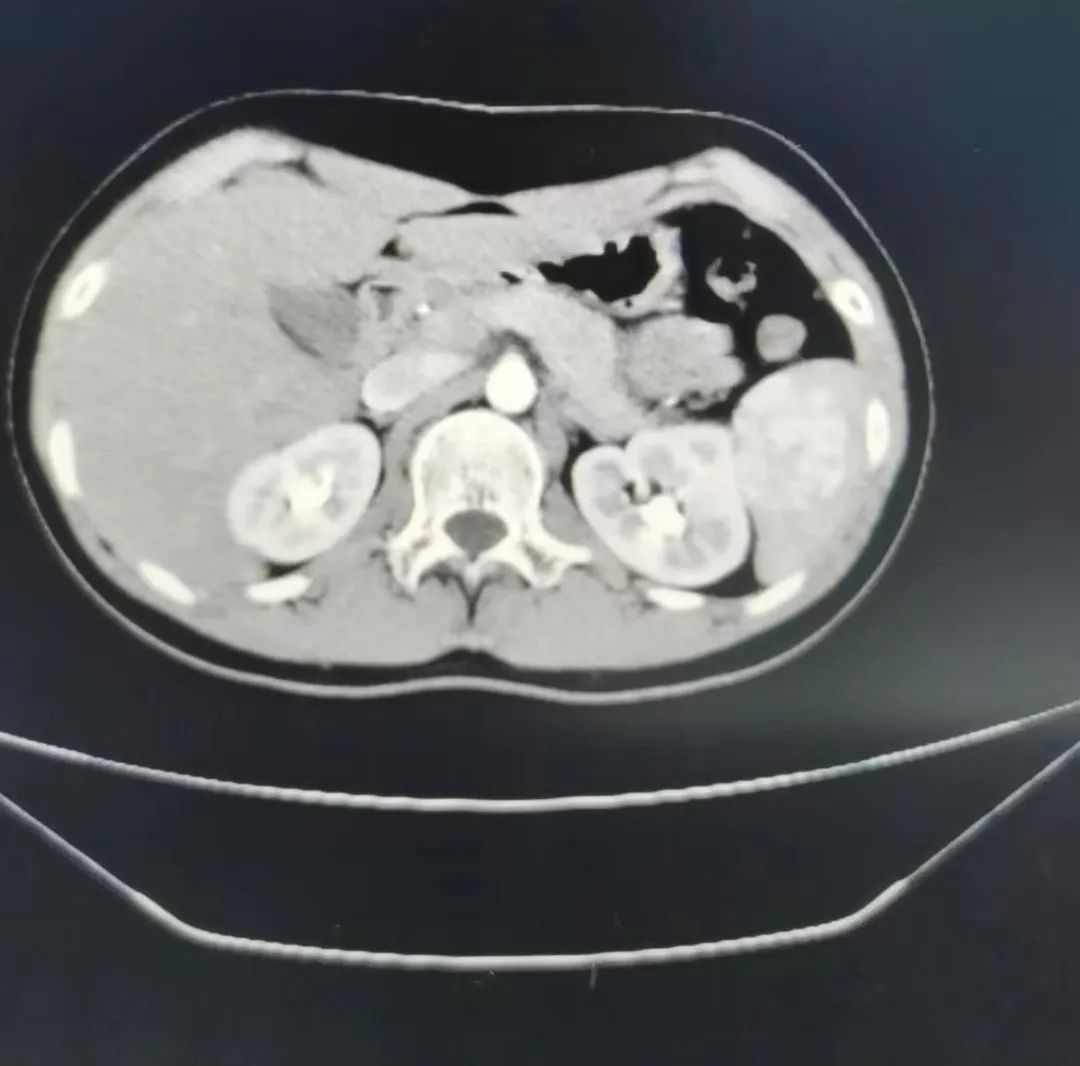

2 个月前,12 岁男童出现反复腹痛、经常性头晕,在当地医院治疗后,症状没有得到缓解且未找到病因。家长立即带孩子前来江西省儿童医院普外科门诊就诊。经全面检查后,接诊医生发现男童脾脏有一处血管瘤,瘤体约 5 cm*4 cm*3 cm,且存在持续增大的生长趋势,至此,男童及家人终于找到了反复引起腹痛和头晕的原因。

张守华博士介绍,脾是人体最大的淋巴器官,具有造血、储血、清除衰老红细胞和进行免疫应答的功能。针对该男童范围如此大的脾血管瘤,以往多实行全脾切除,但术后并发症较多,有血小板进行性上升、血栓、凶险感染、心血管疾病等风险。由于该男童的脾血管瘤位于下极,通过解剖脾门血管动静脉并选择性离断下极脾蒂血管,可以让「保脾」成为可能。